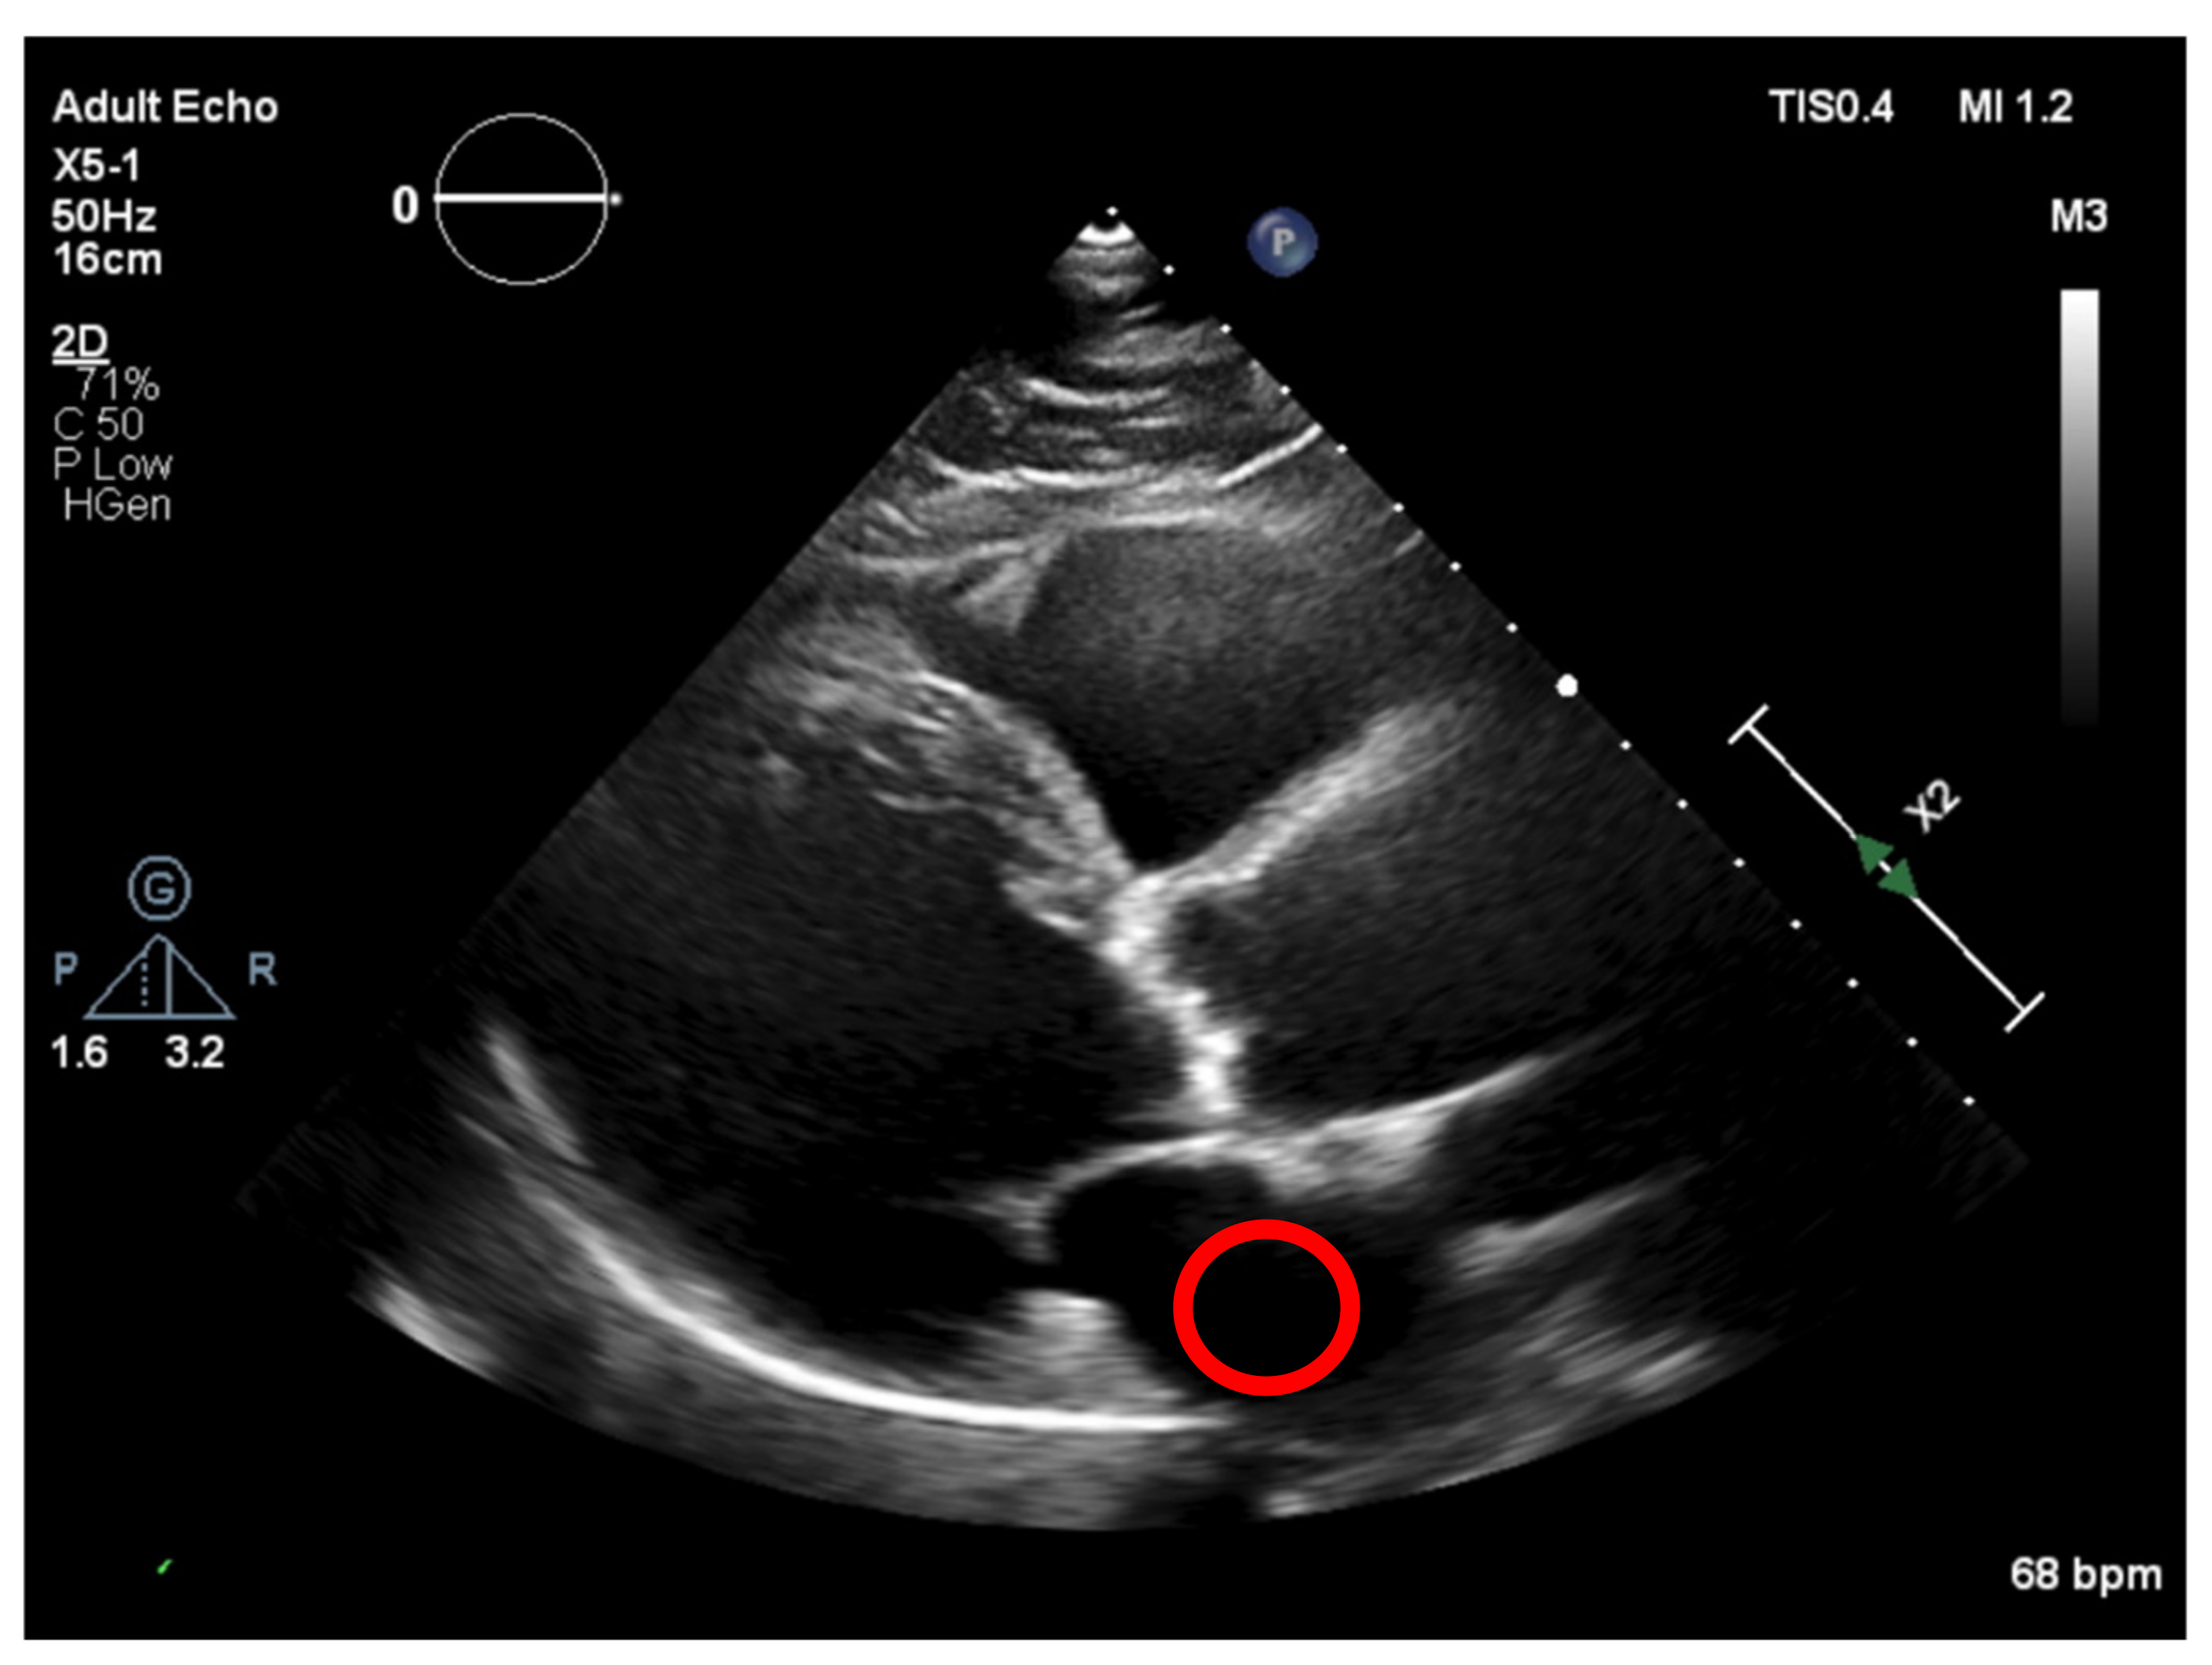

Nevertheless, this simple approach relying solely on histogram equalization leads to poor and inconclusive results in terms of visualizing and extracting the presence of calcium, as shown in Figure 1. The red circle represents where there is calcium on the aortic valve, and in yellow, other structures are marked, which are indistinguishable from each other.

Figure 1. Echocardiography image with CLAHE—The red circle represents the region of interest (ROI) where the calcified aortic valve is located, and in yellow, other structures are marked, which are non-calcified structures.